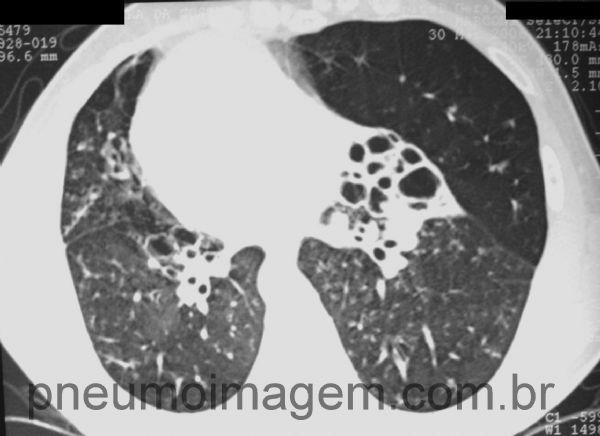

Síndrome de Kartagener. Inversão visceral (dextrocardia), bronquiectasias e sinusite.

Dextrocardia e bronquiectasias. Observe a hiperinsuflação compensatória do lobo inferior, com pobreza vascular.

situs inversus; dextrocardy; bronchiectasis.